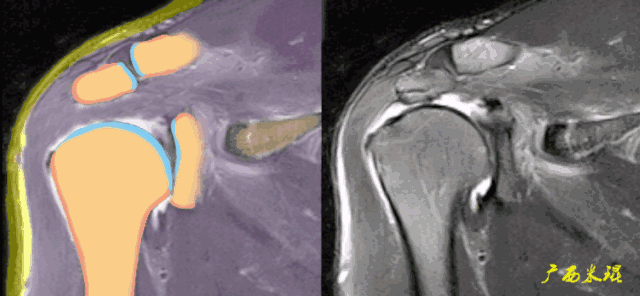

3、邻近组织异常

邻近组织异常包括信号异常和形态异常,是肩袖撕裂的间接征象,对诊断有意义但不能直接诊断肩袖撕裂。邻近组织包括肩峰下滑囊、骨(肩峰、大结节、小结节、喙突)、关节(肩锁关节、盂肱关节)、肱二头肌长头腱等。

a、肩峰下滑囊增大,是肩袖损伤必有的表现。

b、肩峰下滑囊贯通(与关节腔相通),预示着肩袖的完全撕裂。

c、钩状肩峰,发生肩袖撕裂的机会大,但绝不是百分之百。

d、肩峰骨刺,发生肩袖撕裂的机会比钩状肩峰还要大,必须认真阅看,肩峰骨刺在斜矢状位上显示得非常清楚。

肩峰骨刺在斜冠状位上能够看到,应该认真观察并且留意其对应的肩袖面。

e、肱骨大结节骨赘增生,一般是较久的反复的撞击造成,一旦出现,肩袖撕裂的可能性极高。

f、肱骨大结节部位的皮质骨下囊肿,也是长时间撞击的一种表现,不但是肩袖撕裂重要的间接征象,也是肩袖撕裂手术治疗的一个难点。

g、肱骨大结节的部分缺损是长时间严重撞击的表现,在斜冠状位发现缺损的同时,一般都能看到肩袖的中断和回缩。

h、肩锁关节增生水肿,单独的肩锁关节炎也有此表现,所以这只是诊断的间接征象,肩袖撕裂需要结合其他征象才能确诊。

i、盂肱关节关系异常,在斜冠状面上看到肱骨头的上移,肩峰与肱骨头间隙狭窄是肩袖巨大撕裂的表现。

盂肱关节关系异常在轴位片上也可能看到,一般是由于肩胛下肌或冈下肌和小圆肌的撕裂后力量不平衡所造成。

j、盂肱关节骨性关节炎,肩袖撕裂的晚期会出现,其他很多原因也会出现,所以只是诊断的间接征象。

k、肱二头肌长头腱撕裂以及滑脱常常是肩袖撕裂的一种病理改变或者合并症,当我们看见这些改变,也应该认真的观察肩袖是否有撕裂。